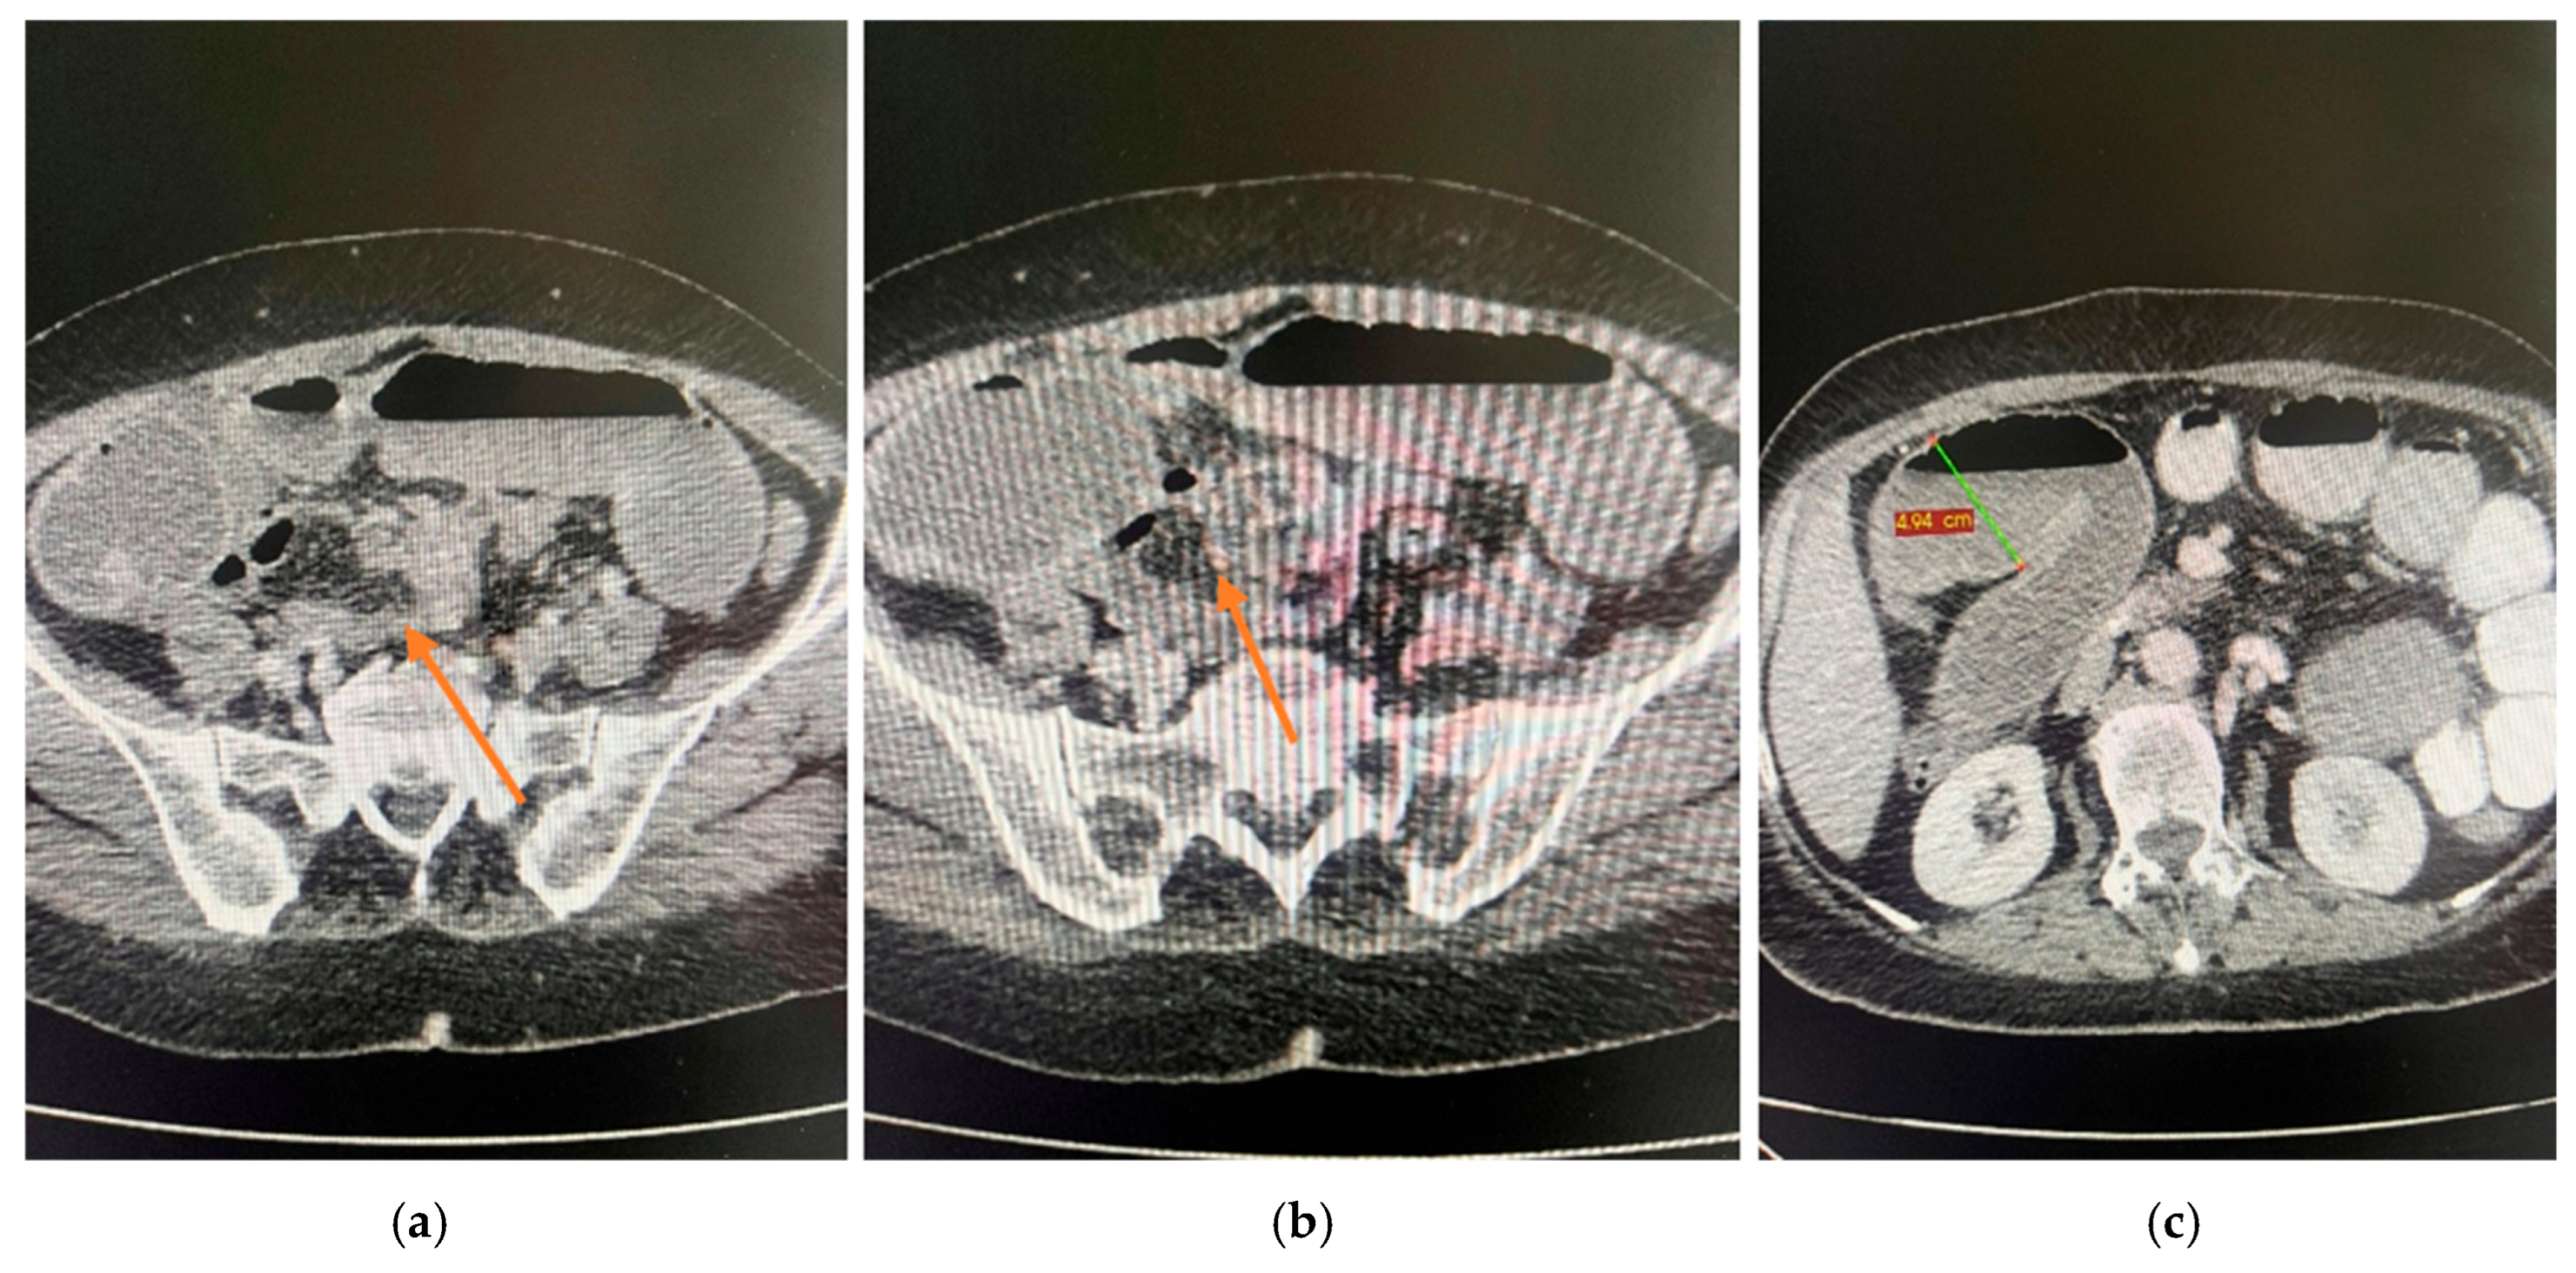

2.4. Diagnostic Assessment

2.5. Therapeutic Intervention